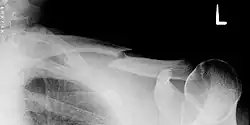

![]() Złamanie obojczyka w zdjęciu RTG | |

Złamanie obojczyka – przerwanie ciągłości kości w obrębie objczyka. Może być z przemieszczeniem lub bez. Wiąże się z wystąpieniem bólu i obrzęku w miejscu złamania. Może wystąpić jako jedno z powikłań porodowych[1]. Złamanie obojczyka oraz zalecenia związane z leczeniem opisał już Hipokrates w 400 p.n.e.[2].